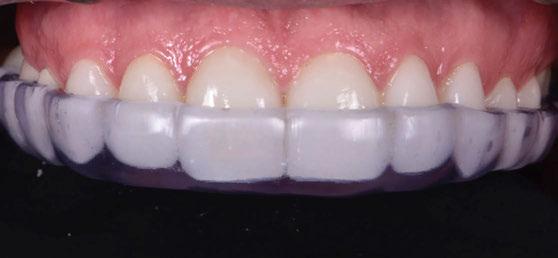

Finalmente, las restauraciones se cementaron adhesivamente (Figuras 31-35). En las piezas 16 y 17 se realizaron restauraciones cementoatornilladas como última fase de tratamiento. Se recomendó al paciente una férula de protección superior la cual fue elaborada mediante un flujo de trabajo digital (Figura 36)

Figura 36. Férula de protección.